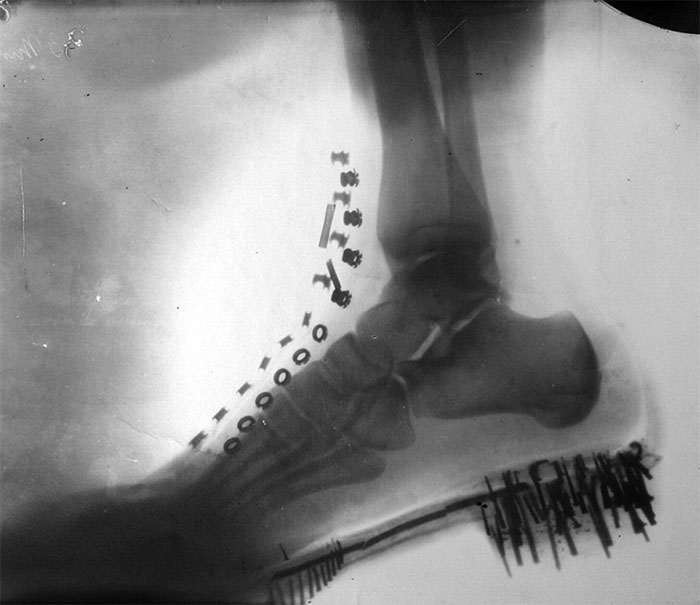

Не шутите с гвоздезабивным пистолетом